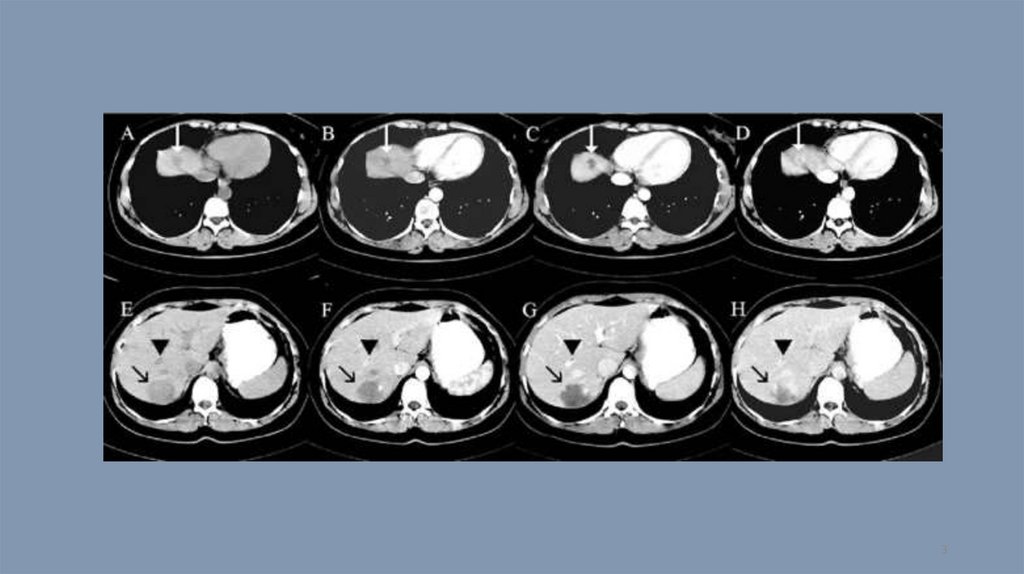

Компьютерная томография. Тест 14